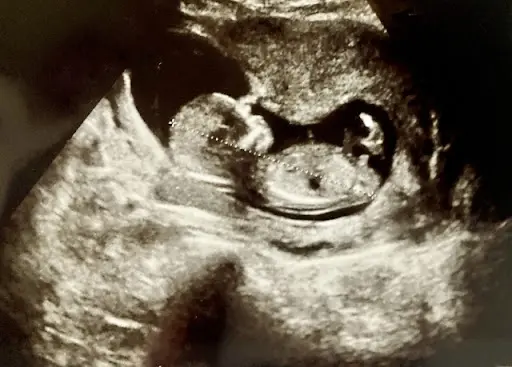

QCan it be diagnosed by amniocentesis and ultrasound?DiGeorge syndrome can be diagnosed by amniocentesis and ultrasound.

An amniotic fluid test is performed if the NIPT is positive. The amniotic fluid test is one of the definitive diagnostic procedures. A definitive diagnosis is one that clearly determines the type and cause of the disease, so that doctors can plan a course of treatment.

Echocardiography, also known as ultrasound, is a test to look for organ abnormalities that may appear in DiGeorge syndrome. Most are performed after birth. It is easier to perform an ultrasound on a newborn baby after birth to detect cardiac and renal malformations. Prenatal tests can also look for cardiac and renal malformations in the foetus, but are considered more difficult.